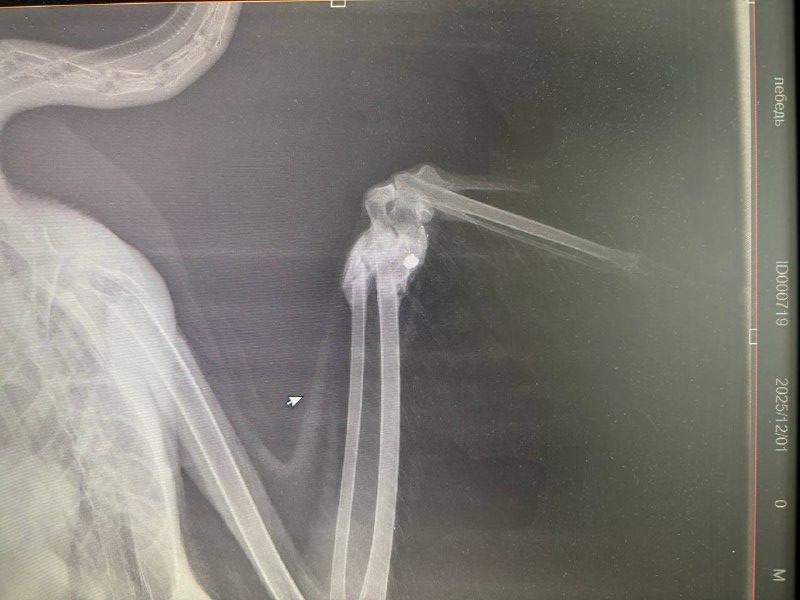

Инспекторы бережно извлекли его из водоема для обследования его состояния и определения дальнейшей судьбы. Ветеринары диагностировали мелкооскольчатый перелом локтевой и лучевой костей крыла после проведения клинического осмотра и рентгенографии. Предположительно, лебедя подстрелили.